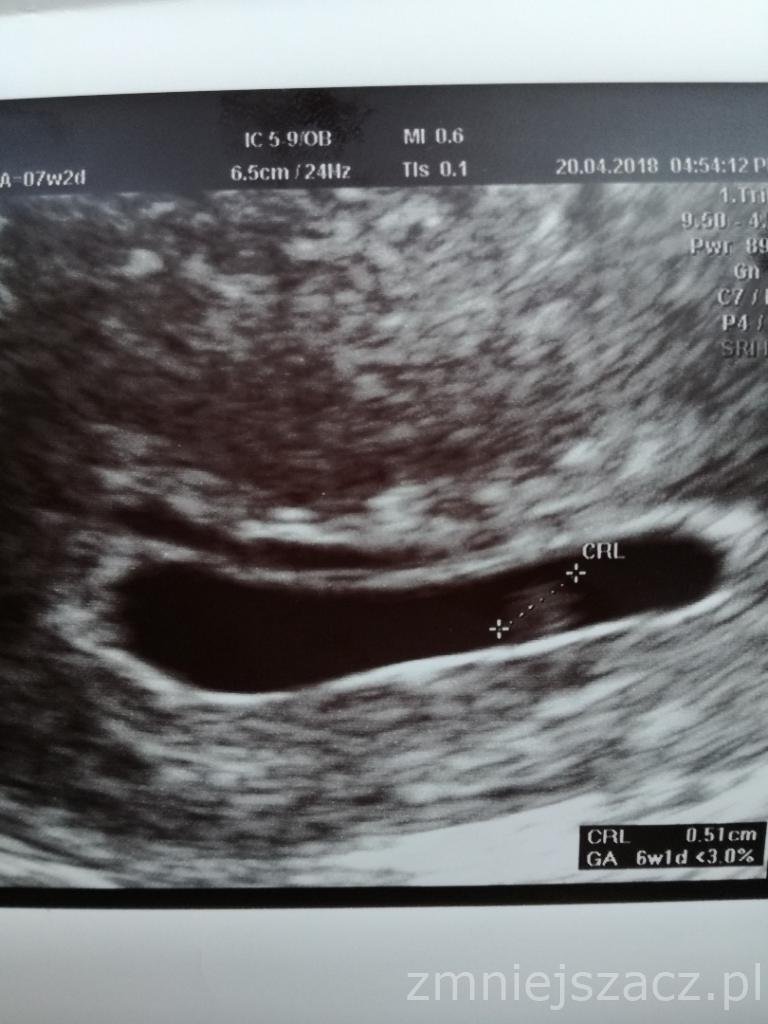

No to nieźle to czekamy co na następnej będzieDziewczyny bylam wczoraj tak szczrsliwa, ze zapomniałam dać zdjecia. Widzicie ten drugi płaski pecherzyk u gory? To najprawdopodobniej drugi pecherzyk ciazowyale pusty. P. Doktor powiedzial, ze gdyby mialabyc ciaza blizniacza to na tym etapie raczej byloby juz cos widac, no ale z drugiej strony stwierdzil, ze nie takie cuda juz widzial i wszystko wyjasni sie na kolejnej wizycie

Zobacz załącznik 848921